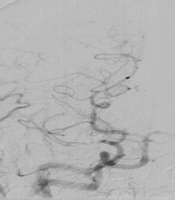

Enhancing Cardiopulmonary Resuscitation: A Hemodynamic Approach Using Doppler Ultrasound and Echocardiography